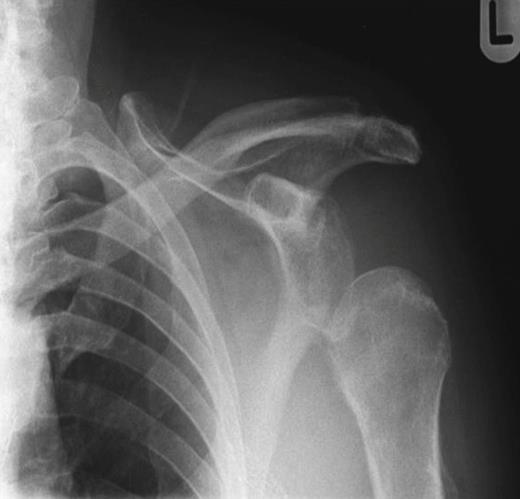

An 80 year old man sustained an injury to his left shoulder during a fall. As a result of the intoxication the history of the mechanism of injury was poor. The gentleman was not taking aspirin or other anticoagulants. On examination movements of the shoulder girdle were reduced secondary to pain. Neurological examination of the left upper limb was normal, as was vascular state of the left arm. X-rays of the joint showed no bony injury (figure 1). Ultrasound showed a large periarticular haemarthrosis and an associated tear in the rotator cuff. Conservative therapy was adopted and the patient was discharged to the rehabilitation ward after two weeks.